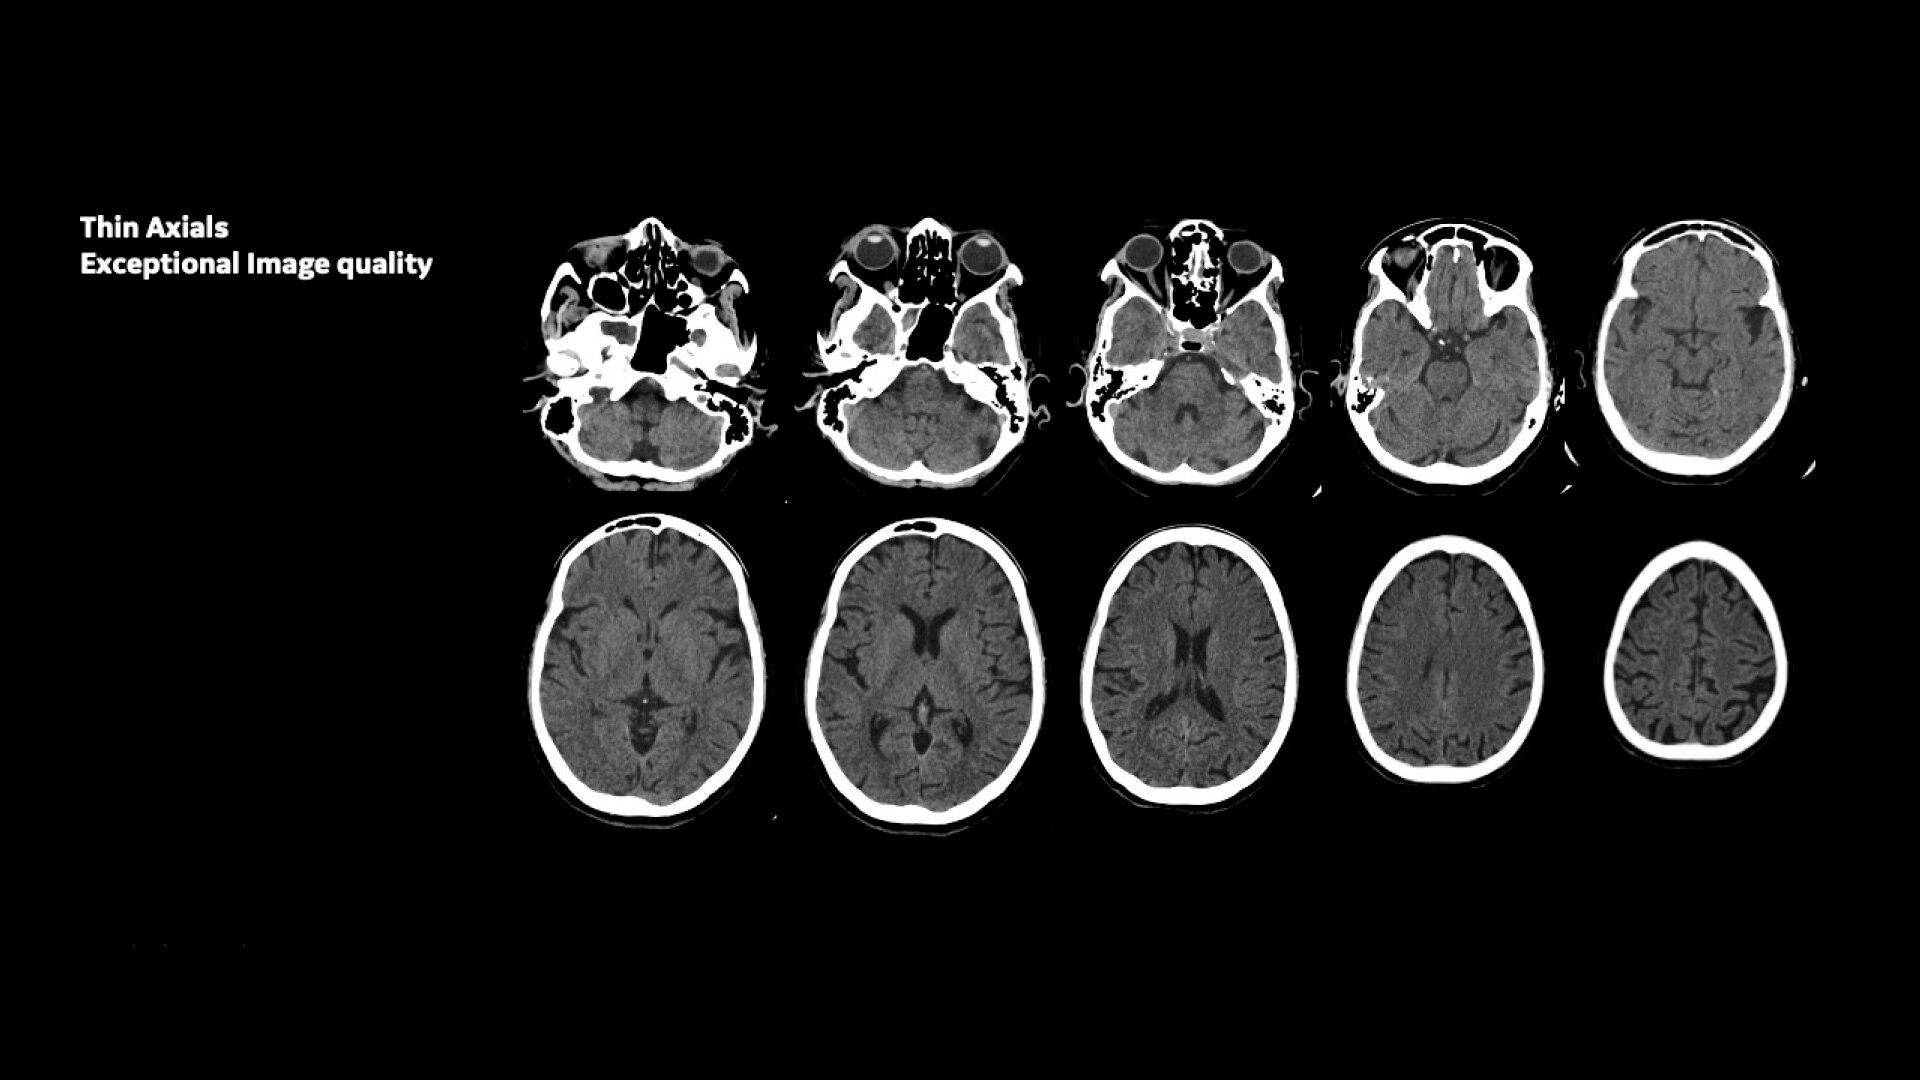

Improve your diagnostic capabilities with the innovative Clarity Imaging Chain and up to 30% enhanced image quality*

Innovative imaging chain – The Clarity Imaging Chain consists of the Atlas Panel Detector, X-ray Tube, Compact High-voltage Generator, and optional ASiR reconstruction. It delivers high spatial resolution with low noise and less artifact to meet various customer needs in real clinical situations.

IQ Enhance – Reduces helical artifacts, which is important for image quality of thin-slice helical scans.